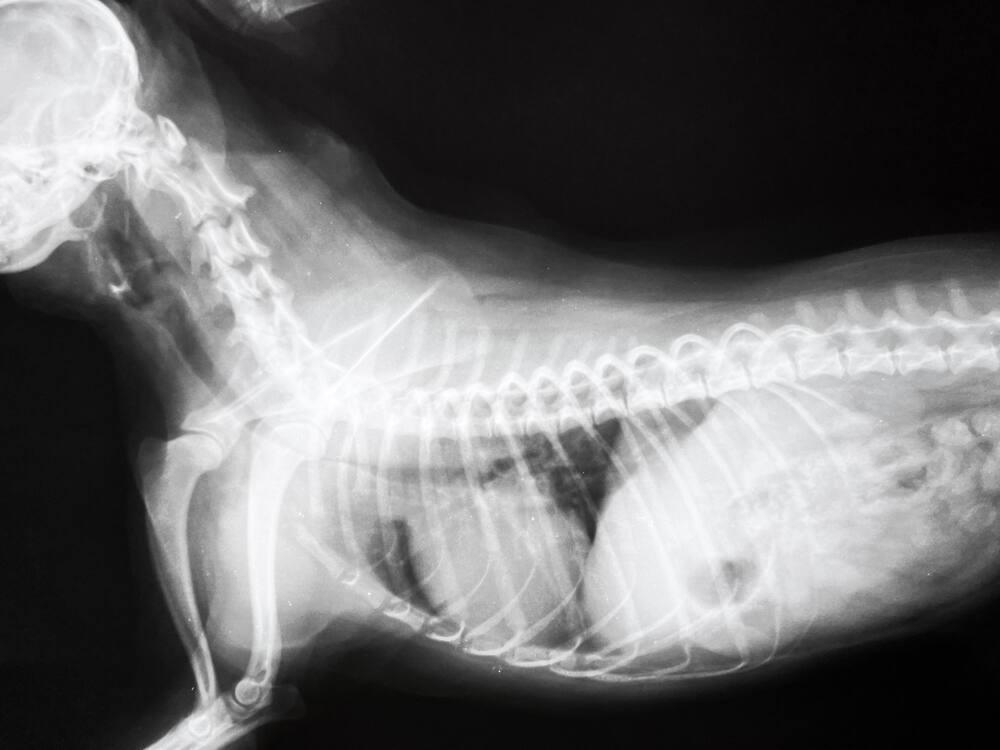

Zapadanie tchawicy u psa diagnozowane jest na podstawie badania RTG, endoskopii, a czasem także badania USG. Najdokładniejsze jest badanie endoskopowe, które pozwala na ocenę stopnia spłaszczenia tchawicy i zaawansowania choroby w czterostopniowej skali.